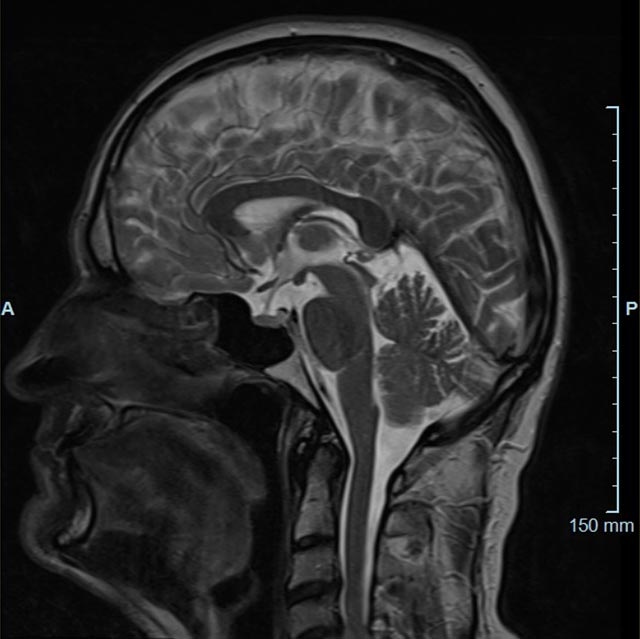

Magnetresonanztomographie (MRT)

Die Magnetresonanztomographie (MRT) wurde als bildgebendes Verfahren ab 1973 vor allem von Paul C. Lauterbur und Sir Peter Mansfield entwickelt.

In den letzten Jahren hat sich die Methode stark weiterentwickelt und in der medizinischen Diagnostik etabliert.

Im Magnetresonanztomographen liegt die zu untersuchende Person in einem starken, homogenen Magnetfeld. Dieses Magnetfeld bewirkt eine gemeinsame Ausrichtung der Wasserstoffprotonen im Körper entlang der Längsachse des Magnetfeldes. Wird nun diesen Teilchen Energie in Form von Radiowellen in einer genau abgegrenzten Frequenz zugeführt, so werden sie aus ihrer ursprünglichen Orientierung abgelenkt.

Die zugeführte Energie wird in gewebespezifischer Weise wieder abgegeben. Ein hochempfindliches Computersystem misst die unterschiedliche Energieabgabe und setzt sie in Bildinformationen um. Jede Körperregion kann somit durch Schnittbilder in allen Raumebenen oder durch dreidimensionale Rekonstruktionen mit einem exzellenten Weichteilkontrast dargestellt werden. Es besteht keine Belastung durch Röntgenstrahlen.